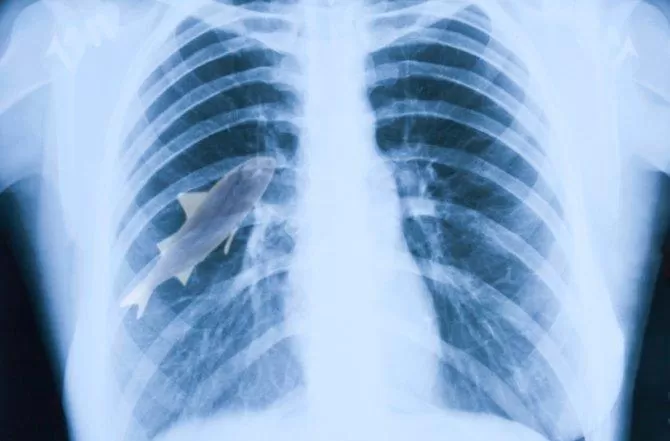

EN SU CUERPO. El pez quedó en el pulmón. FOTO TOMADA DE ABC.ES

El animal terminó en el pulmón izquierdo de Anil, que fue internado de urgencia con graves problemas de respiración. Los médicos lograron extraer el pez de su cuerpo y estabilizar sus niveles de oxígeno en sangre, que habían disminuido a puntos críticos y por surte ahora está fuera de peligro. (Especia-ABC.es)